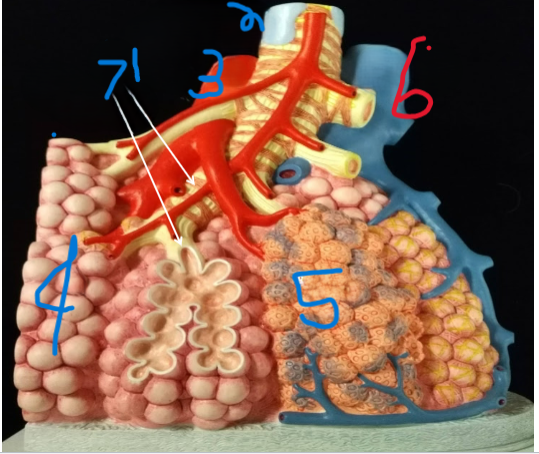

Terminal Bronchiole

What is depicted by #1

Bronchiole with smooth muscle

What is depicted by #2

Pulmonary vein, branch

What is depicted by #3

Alveoli

What is depicted by #4

Pulmonary capillaries

What is depicted by #5

Pulmonary artery, branch

What is depicted by #6

Respiratory Bronchiole

What is depicted by #7